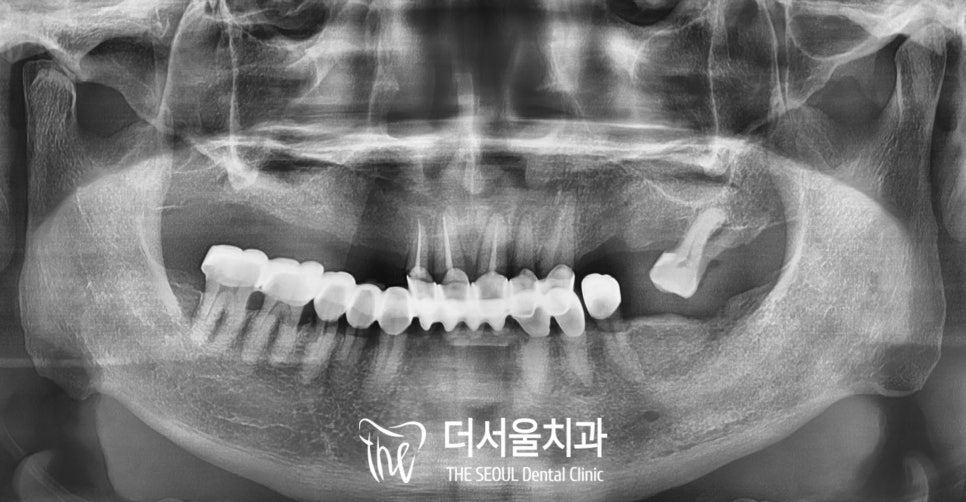

구강을 살펴보면

곳곳에 비어있는 공간이 존재하며

그 자리로 부분 틀니를

사용하고 계셨던 것을 알 수 있습니다.

그리고 부러진 것 같다고 하신

앞니를 보기 위해

우선 전체 구강이 다 나오는

파노라마 사진을 찍어

살펴보았습니다.

눈으로 보이지 않는

치조골의 모습을 확인할 수 있으며

전반적인 치주 상태를 알 수 있습니다.